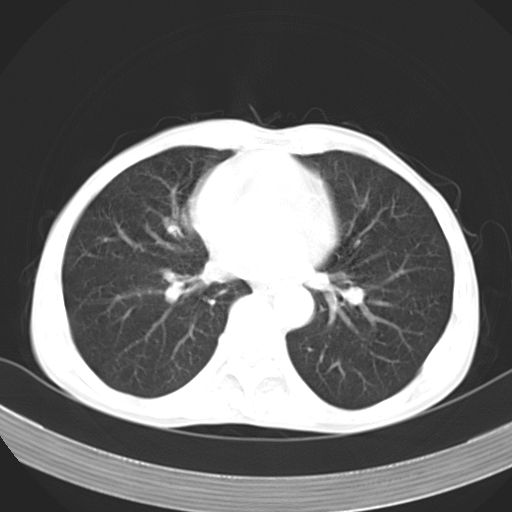

以下是引用zhangzhongshou在2007-5-24 12:55:00的发言:[br]1、右肺中叶中心型肺癌并右肺门、隆突下、纵隔淋巴结转移。右肺中叶阻塞性肺炎。

以下是引用苯小孩在2007-5-24 12:47:00的发言:[br]右侧肺门处不均匀密度软组织块影,远端肺组织见斑片模糊影,纵隔内淋巴结明显肿大,边界不清.<纵隔窗第12层面支气管内似见软组织结节>[br]考虑:1、右侧中央性肺癌并阻塞性肺炎并纵隔淋巴结转移可能性大.建议强化或纤支镜进一步检查.[br]2、隆突下淋巴结肿大/食道病变?请做鉴别检查.

以下是引用jw-830在2007-5-24 15:24:00的发言:[br][br] [br] 考虑右肺中央型肺癌并阻塞性炎症,右肺门及纵隔淋巴结转移。 [br] [br][br]